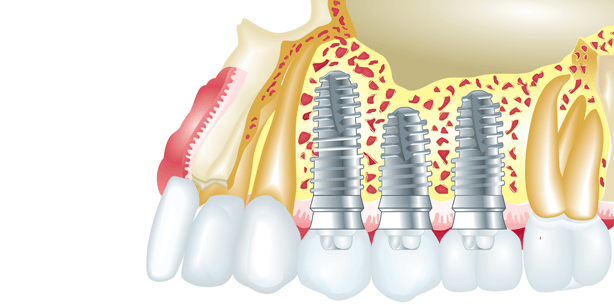

Foto: © kustan - Fotolia

Diabetes mellitus gilt als Risikofaktor für Parodontitis und periimplantäre Erkrankungen. Deshalb wird Patienten mit Stoffwechselstörungen, wie der Zuckerkrankheit, oft von Implantaten abgeraten. Denn Zuckerschwankungen beeinträchtigen unter anderem die Einheilung der gesetzten Implantate.

Eine Studie, durchgeführt am UT Health Science Center in San Antonio, die in der Dezember-Ausgabe des Journal of the American Dental Association erschienen ist, lässt nun hoffen. In ihrem publizierten Beitrag berichten die Forscher, dass die Erfolgsquote von Implantaten bei Diabetikern genauso hoch sei wie bei gesunden Menschen.

Für die Untersuchung wurden 110 Patienten, darunter Diabetiker, Nicht-Diabetiker und schlecht eingestellte Diabetiker, je zwei Implantate im Unterkiefer gesetzt und über den Zeitraum von einem Jahr beobachtet – mit dem Ergebnis, dass sowohl Diabetiker als auch Nicht-Diabetiker eine hundertprozentige Erfolgsrate verzeichneten. Die Ergebnisse der Studie zeigten keine signifikanten Unterschiede zwischen der nicht-diabetischen und der gut kontrollierten Diabetes-Gruppe. Lediglich die Patienten mit schlecht eingestellter Diabetes benötigten eine längere Einheilzeit, sodass diese – im Sinne der Vergleichbarkeit – bei allen Gruppen vier statt zwei Monate betrug, berichtet Studienleiter Thomas Oates, DMD, Ph.D. Allen Patienten wurde begleitend Antibiotika und Chlorhexidingluconat verabreicht, um das Infektionsrisiko im Mund nach der OP zu minimieren.